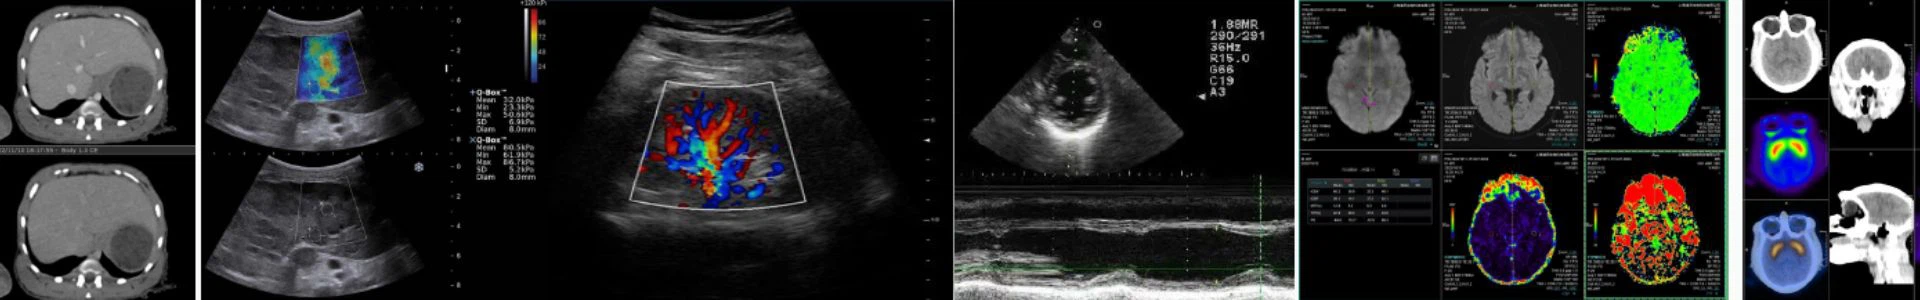

„Prisys Biotechnologies“ įdiegė pirmaujančią vaizdu valdomą vaistų pristatymo platformą, pirmą tokią Kinijoje, kad optimizuotų tiriamųjų genų, ląstelių ir kitų terapijų tiekimą tiesiai į smegenų parenchimą ikiklinikinėms reikmėms. Su Prisys vidine MR vaizdavimo sistema, naujoji technologija sujungia specializuotą su MRT suderinamą aparatinę ir programinę įrangą, kad būtų galima planuoti chirurgines trajektorijas ir nukreipti infuzijos kaniulę į tikslą. Šios minimaliai invazinės procedūros metu galima optimizuoti taikymą ir dozavimą, siekiant pagerinti saugumą ir veiksmingumą.

„ClearPoint®“ sistema sukelia revoliuciją neurochirurgijos srityje, teikdama intraprocedūrines MRT gaires, o tai užtikrina neprilygstamą tikslumą ir tikslumą smegenyse tiekiant terapines medžiagas.

„ClearPoint“ sistema yra saugus, efektyvus ir patikimas būdas pateikti naujus gydymo būdus konkrečioms smegenų struktūroms, naudojant integruotą MR smegenų kartografavimą. Sukaupti atvejų tyrimai tiek su žmonėmis, tiek su dideliais eksperimentiniais gyvūnais ir gausūs klinikiniai įrodymai įrodė jo veiksmingumą, todėl tapo geriausiu atitinkamų terapinių priemonių, tokių kaip mažos molekulės, biologiniai preparatai, ląstelių ir genų terapija, nanodalelės ir nukleino rūgštis, transliacinių tyrimų ir plėtros sprendimu. - pagrįstos terapijos. Pagrindiniai pranašumai apima:

Naudodamas intraprocedūrinę MRT valdomą technologiją, Prisys siekia suteikti unikalią patirtį ir pažangų ikiklinikinį sprendimą jūsų vaistų tyrimams ir plėtrai.Naudodami ClearPoint sistemą galite atlikti įvairias procedūras, pavyzdžiui:

„ClearPoint System“ yra naujausia neuronavigacijos sistema, kuri naudoja realiojo laiko MRT nurodymus, kad saugiai ir tiksliai pristatytų smegenis gydomąsias priemones. Lyginant su kitais metodais ar sistemomis, ClearPoint sistema turi keletą privalumų, tokių kaip: